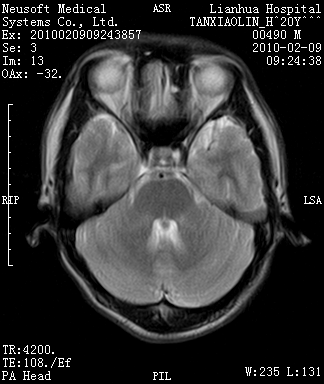

20岁男性患者,平时偶有头痛而无其他不适,现因持续头痛服药后无缓解而来院就诊。

松果体囊肿?

松果体区占位继发轻度脑积水?该患者有ct资料,我已发上。

考虑松果体囊肿。